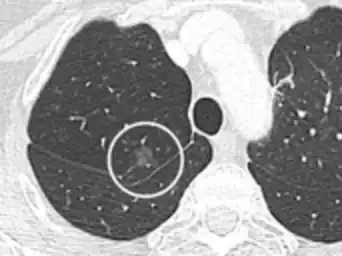

PET scan

If there is an intermediate risk of malignancy, further imaging with positron emission tomography (PET scan) is appropriate (if available). It can be done simultaneously as a CT scan in the form of PET-CT. Around 95% of patients with a malignant nodule will have an abnormal PET scan, while around 78% of patients with a benign nodule will look normal on PET (this is the test sensitivity and specificity).[15] Thus, an abnormal PET scan will reliably pick up cancer, but several other types of nodules (inflammatory or infectious, for example) will also show up on a PET scan. If the nodule has a diameter of less than one centimeter, PET scans are often avoided because of an increased risk of falsely normal results.[15][16][17] Cancerous lesions usually have a high metabolism on PET, as demonstrated by their high uptake of FDG (a radioactive sugar).

PET-CT of a tuberculoma.

PET-CT of a tuberculoma.